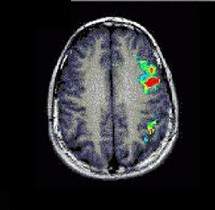

Case 1

Patient Female patient, age 19. Presurgical demonstration of eloquent areas

Paradigm Phonetic fluency

ON: Silent word generation starting with a given letter

OFF: Think of nothing

Results Activation of middle and inferior left frontal gyri, precentral left cortex, left angular gyri, and scattered areas in the parietal lobes.

Comments The main activated area in this phonetic fluency task is the superior aspect of the left inferior frontal gyrus.   In contrast, the main area of activation on tasks requiring generation of verbs is the inferior aspect of Broca's area, along with the anterior insula.